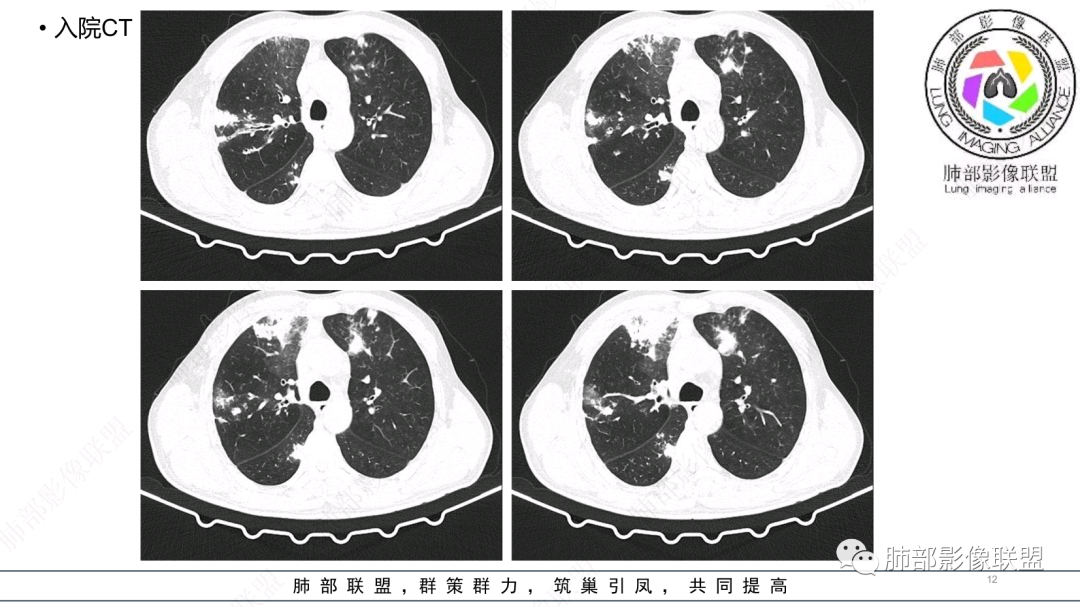

56岁,工作性质:环卫工人。主诉:咳、痰、喘、发病一周。急性起病(或者慢病+AE),呼吸道感染症状。化验指标白细胞、中性、CRP明显升高。影像学显示多灶性,有柱状支扩,囊状支扩等结构肺病,责任细菌主要考虑铜绿假单胞菌,不排除合并其他细菌以阴杆为主;存在树芽影,发热,炎症沿支气管束分布,是否合并TB?真菌?;树芽伴发热支原体感染也要需要考虑进去;全肺多灶性炎症,部分病灶周围有晕,右上叶疑似反晕,内部疑似有丝,右下肺考虑存在粘液栓,加之环卫工工作性质,考虑霉菌,主要考虑曲霉。

支气管壁增厚,晕征明显,病灶沿着支气管纵向分布,结合患者职业,考虑气道侵袭性曲霉。

多发结节,部分结节边缘清楚,部分边缘模糊,支扩合并肉芽肿性炎,奴卡菌与曲霉之间选择。

影像改变为支扩伴气道来源感染,部分实变性伴有小脓肿及钙化,结合PCT及白细胞、中性粒明显增高,符合细菌感染,首先考虑奴卡,绿脓次之,因为临床有喘息、影像实变性有钙化,加上环卫工这一职业史,需要鉴别曲霉或奴卡合并曲霉。

CT:双肺延支气管血管束分布斑片状、团块状、树芽状密度增高影,部分边界模糊,支气管扩张、部分管壁增厚。考虑气道吸入细菌性感染,铜绿假单孢?